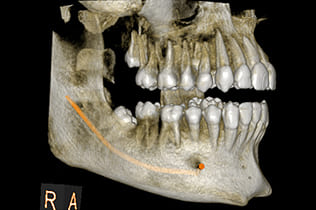

CTと親知らずの抜歯

CTで神経の位置を把握し、リスクを最小限に

親知らずの抜歯は、埋まっている方向や深さ、周囲の神経や血管との位置関係によって難易度やリスクが大きく変わります。CTスキャンにより、親知らずの根の形や生え方、そして下顎管(下歯槽神経や血管が通る管)との位置関係を立体的に把握できます。この詳細な情報があることで、神経損傷などの合併症のリスクを最小限に抑え、より安全かつ迅速な抜歯計画を立てることが可能となります。患者様にとって負担の少ない、安心できる抜歯処置を提供いたします。